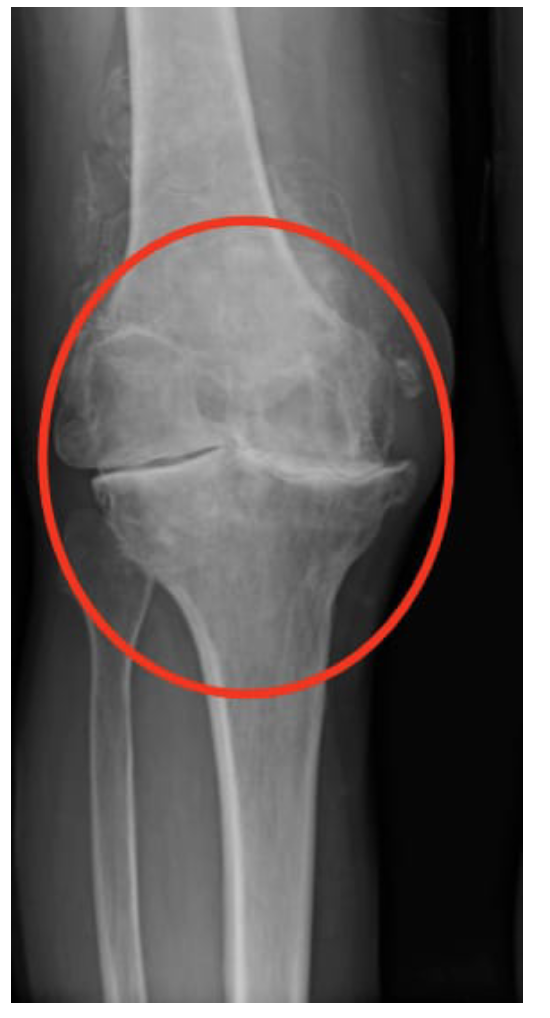

Di altro genere sono le malattie reumatiche degenerative e croniche di cui ne fa da padrone l’artrosi. Questa è una patologia associata all’età. Colpisce in prevalenza anca, ginocchio, spalla e colonna vertebrale. La causa è il deterioramento della cartilagine che riveste le superfici delle ossa a livello articolare. Se sottovalutata le ossa arrivano a sfregarsi tra loro provocando dolore, gonfiore e rigidità. Anche il sovrappeso e l’obesità sono tra i fattori di rischio e incorrono nel peggioramento della patologia.

In questa radiografia al ginocchio possiamo osservare la degenerazione degli strati di cartilagine e lo sfregamento tra il femore e la tibia.

L’artrosi al ginocchio è il risultato di una combinazione di fattori tra cui: peso, avanzamento dell’età ed infortuni. Il soggetto che ne è affetto accusa: rigidità articolare, ridotta mobilità e dolore